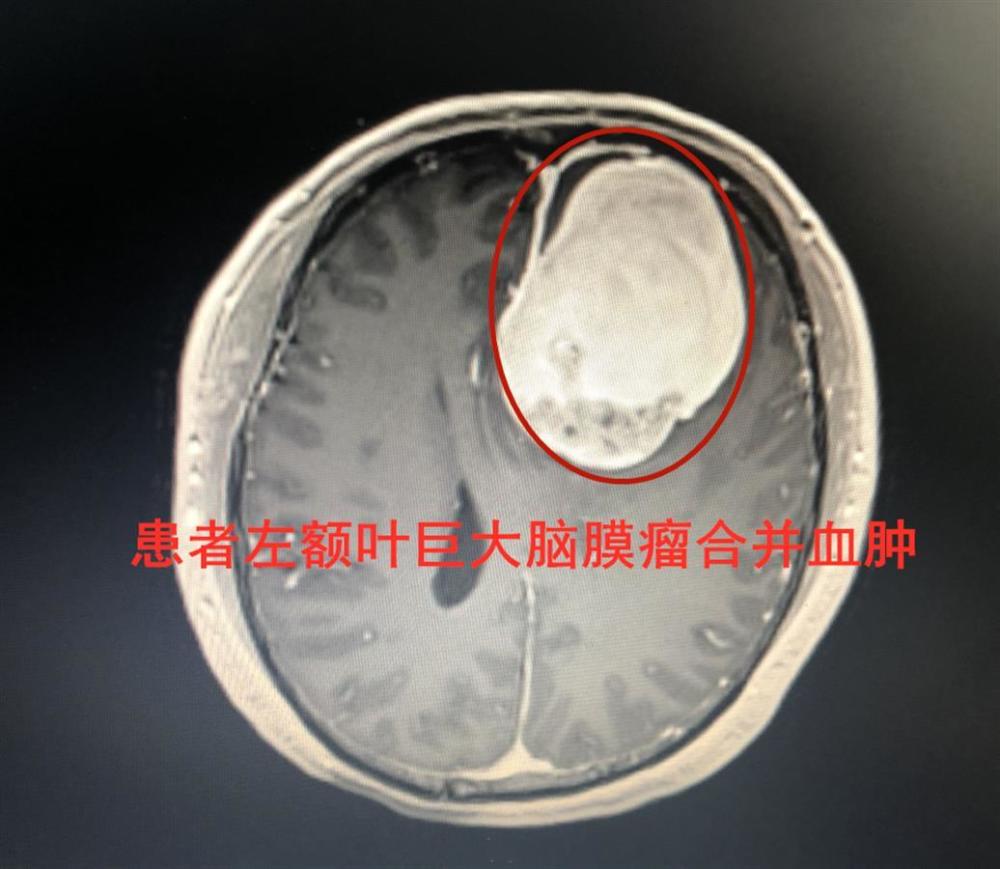

急诊检查显示,患者左侧额部有巨大占位性病变合并血肿,印证了岑波的推测。在稳定生命体征后,该院神经外科团队及时为伍先生进行了手术,并于术中确诊患者是脑肿瘤伴卒中。通过神经导航的精准定位,岑波教授团队一边止血、清血肿,一边小心剥离瘤体,经过6个小时的细致操作,在保护周边正常脑组织和血管的基础上,成功全切了脑瘤。